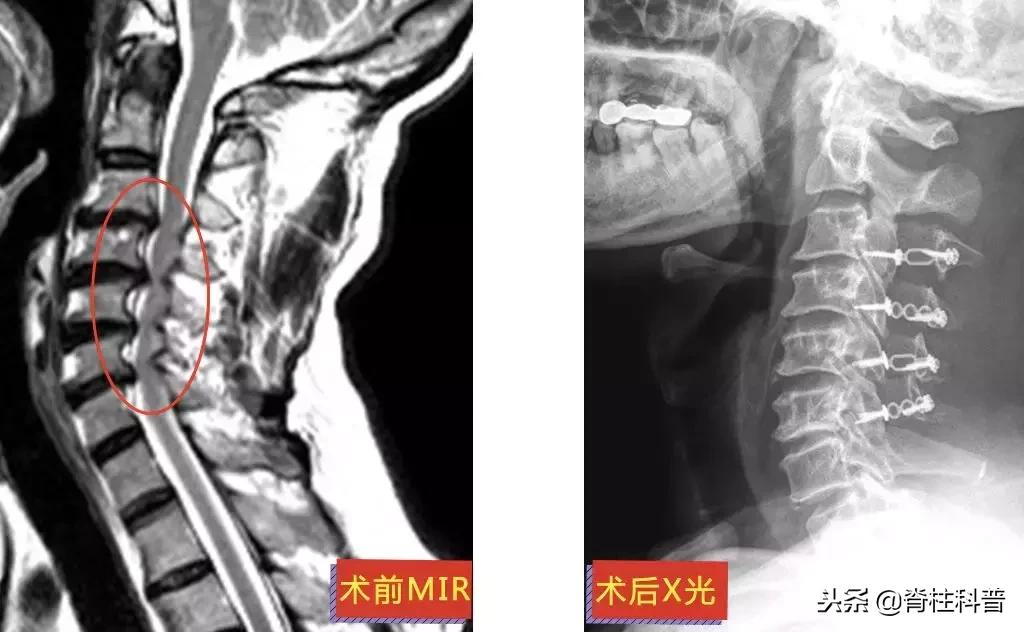

廖四爷(化名)4年前第一次发病:右上肢刮骨样疼痛和乏力。而后的每一次发病,他都只接受牵引等保守治疗,长达4年。可保守治疗的效果逐渐减退。2018年8月23日前来就诊时,廖四爷的右上肢上臂已经出现肌肉萎缩。

▲ 廖四爷:术前MRI与术后X光

11月26日,在张主任的门诊,廖四爷回来复诊。情况还不错,上肢刀割样的疼痛已经消失,照了CT内固定也长得很好,但是萎缩的手臂还没得到恢复,还需要接受康复治疗。